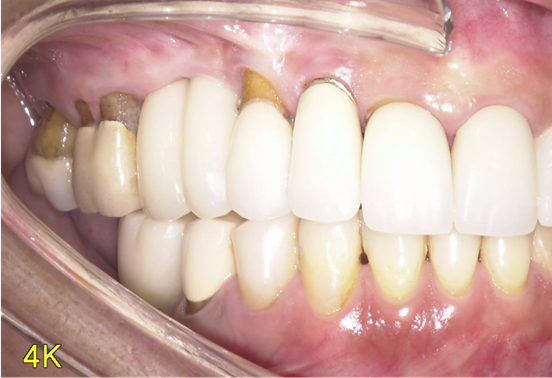

予定通りジルコニアクラウンにて、インプラント修復が行えました。